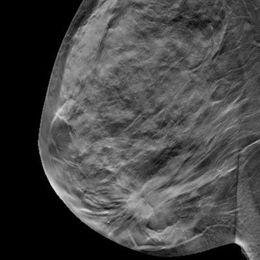

Adding tomosynthesis to digital mammography for breast cancer screening reduces recall rates by 37%, with the technique recording better performance for certain types of breast abnormalities, according to a new study in the January issue of Radiology.

More and more clinical evidence indicates that using digital breast tomosynthesis (DBT) for breast cancer screening reduces recall rates and increases the detection of invasive cancers. Now another benefit of the technology is coming to the fore: Adding DBT to digital mammography helps breast imagers categorize lesions more accurately, according to research presented at ECR 2017.

Screening with digital breast tomosynthesis (DBT) boosts specificity compared with 2D mammography and also finds more cancers, particularly those associated with better prognoses, according to a study published online February 28 in JAMA Oncology.

Breast-cancer screening with three-dimensional imaging finds more invasive cancers and yields fewer false alarms than standard digital mammograms alone, according to a large new study in the Journal of the American Medical Association.